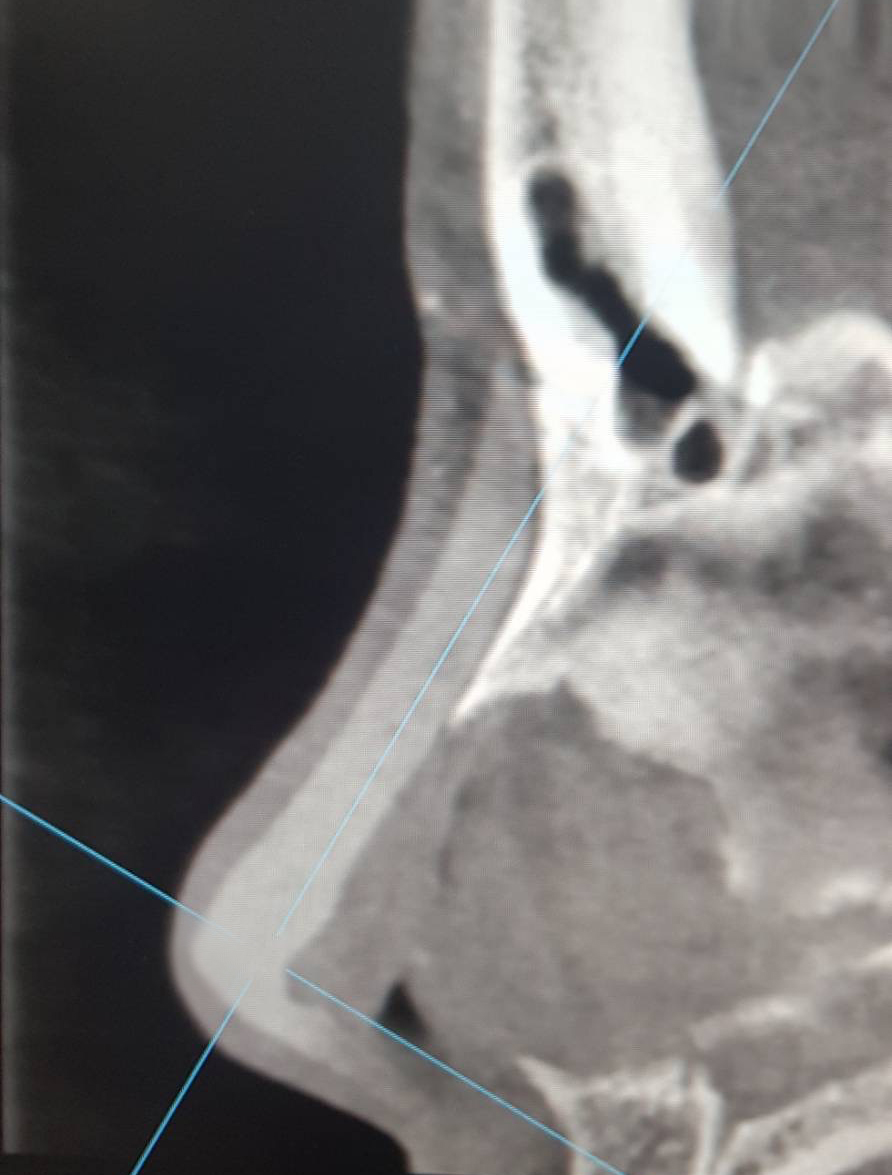

1 ตรวจการเบี้ยวเอียง ปัญหาใหญ่ของการเสริมจมูก ไม่ว่าจะเป็นแบบ openหรือ closed rhinoplasty ก็คือ การเอียง,เบี้ยว คำตอบของผู้ให้กับผู้รับบริการ ที่ไม่ตรงกัน เรามีคำตอบและพิสูจน์ได้ด้วยตาคุณเอง 100% ไม่ว่าจะเป็นที่ไหน โคนหรือปลายจมูก? มากหรือน้อย?

ในกรณีเอียงไม่มาก อาจเป็นสาเหตุให้แกนจมูกใหญ่ หรือ รูจมูกไม่เท่ากันได้ เราสามารถตรวจได้อย่างมั่นใจจากการเห็นภายใน โดยไม่ขึ้นกับอาการบวม เหมือนการตรวจด้วยการมองหรือการคลำ

2 ตรวจดูทรงซิลิโคน จมูกไม่สวยซักที CTบอกได้ เพราะ การตรวจด้วยเครื่องเอกซเรย์คอมพิวเตอร์ความละเอียดสูง สามารถบอกได้ว่าปัญหาความไม่สวยเกิดจากอะไร ทรงSILICONEจมูก ยาวหรือสั้นเกินไป SILICONEตรงหรือโก่ง หัวใหญ่หัวเล็ก การตรวจด้วยเครื่องเอกซเรย์คอมพิวเตอร์ความละเอียดสูง บอกได้ทั้งหมด จะเห็นว่ารูปทรงของSILICONE เมื่อเสริมเข้ามาจริงๆแล้ว ยังต้องมีการปรับตัวให้เข้ากับเนื้อเยื่อรอบด้านทำให้ไม่สามารถประเมินจากภายนอกเพียงอย่างเดียวได้

3 ความเสี่ยงของการทะลุ ในกรณี มีการดันของซิลิโคนมากเกินไปจนผิวหนังบางขึ้น การตรวจด้วยเครื่องเอกซเรย์คอมพิวเตอร์ความละเอียดสูง สามารถบอกได้ โดยเฉพาะอย่างยิ่งการทะลุจากด้านในรูจมูก พราะส่วนใหญ่ของการทะลุไม่ได้เกิดบริเวณผิวด้านนอก แต่เกิดด้านในรูจมูก ซึ่งยากต่อการตรวจสอบ